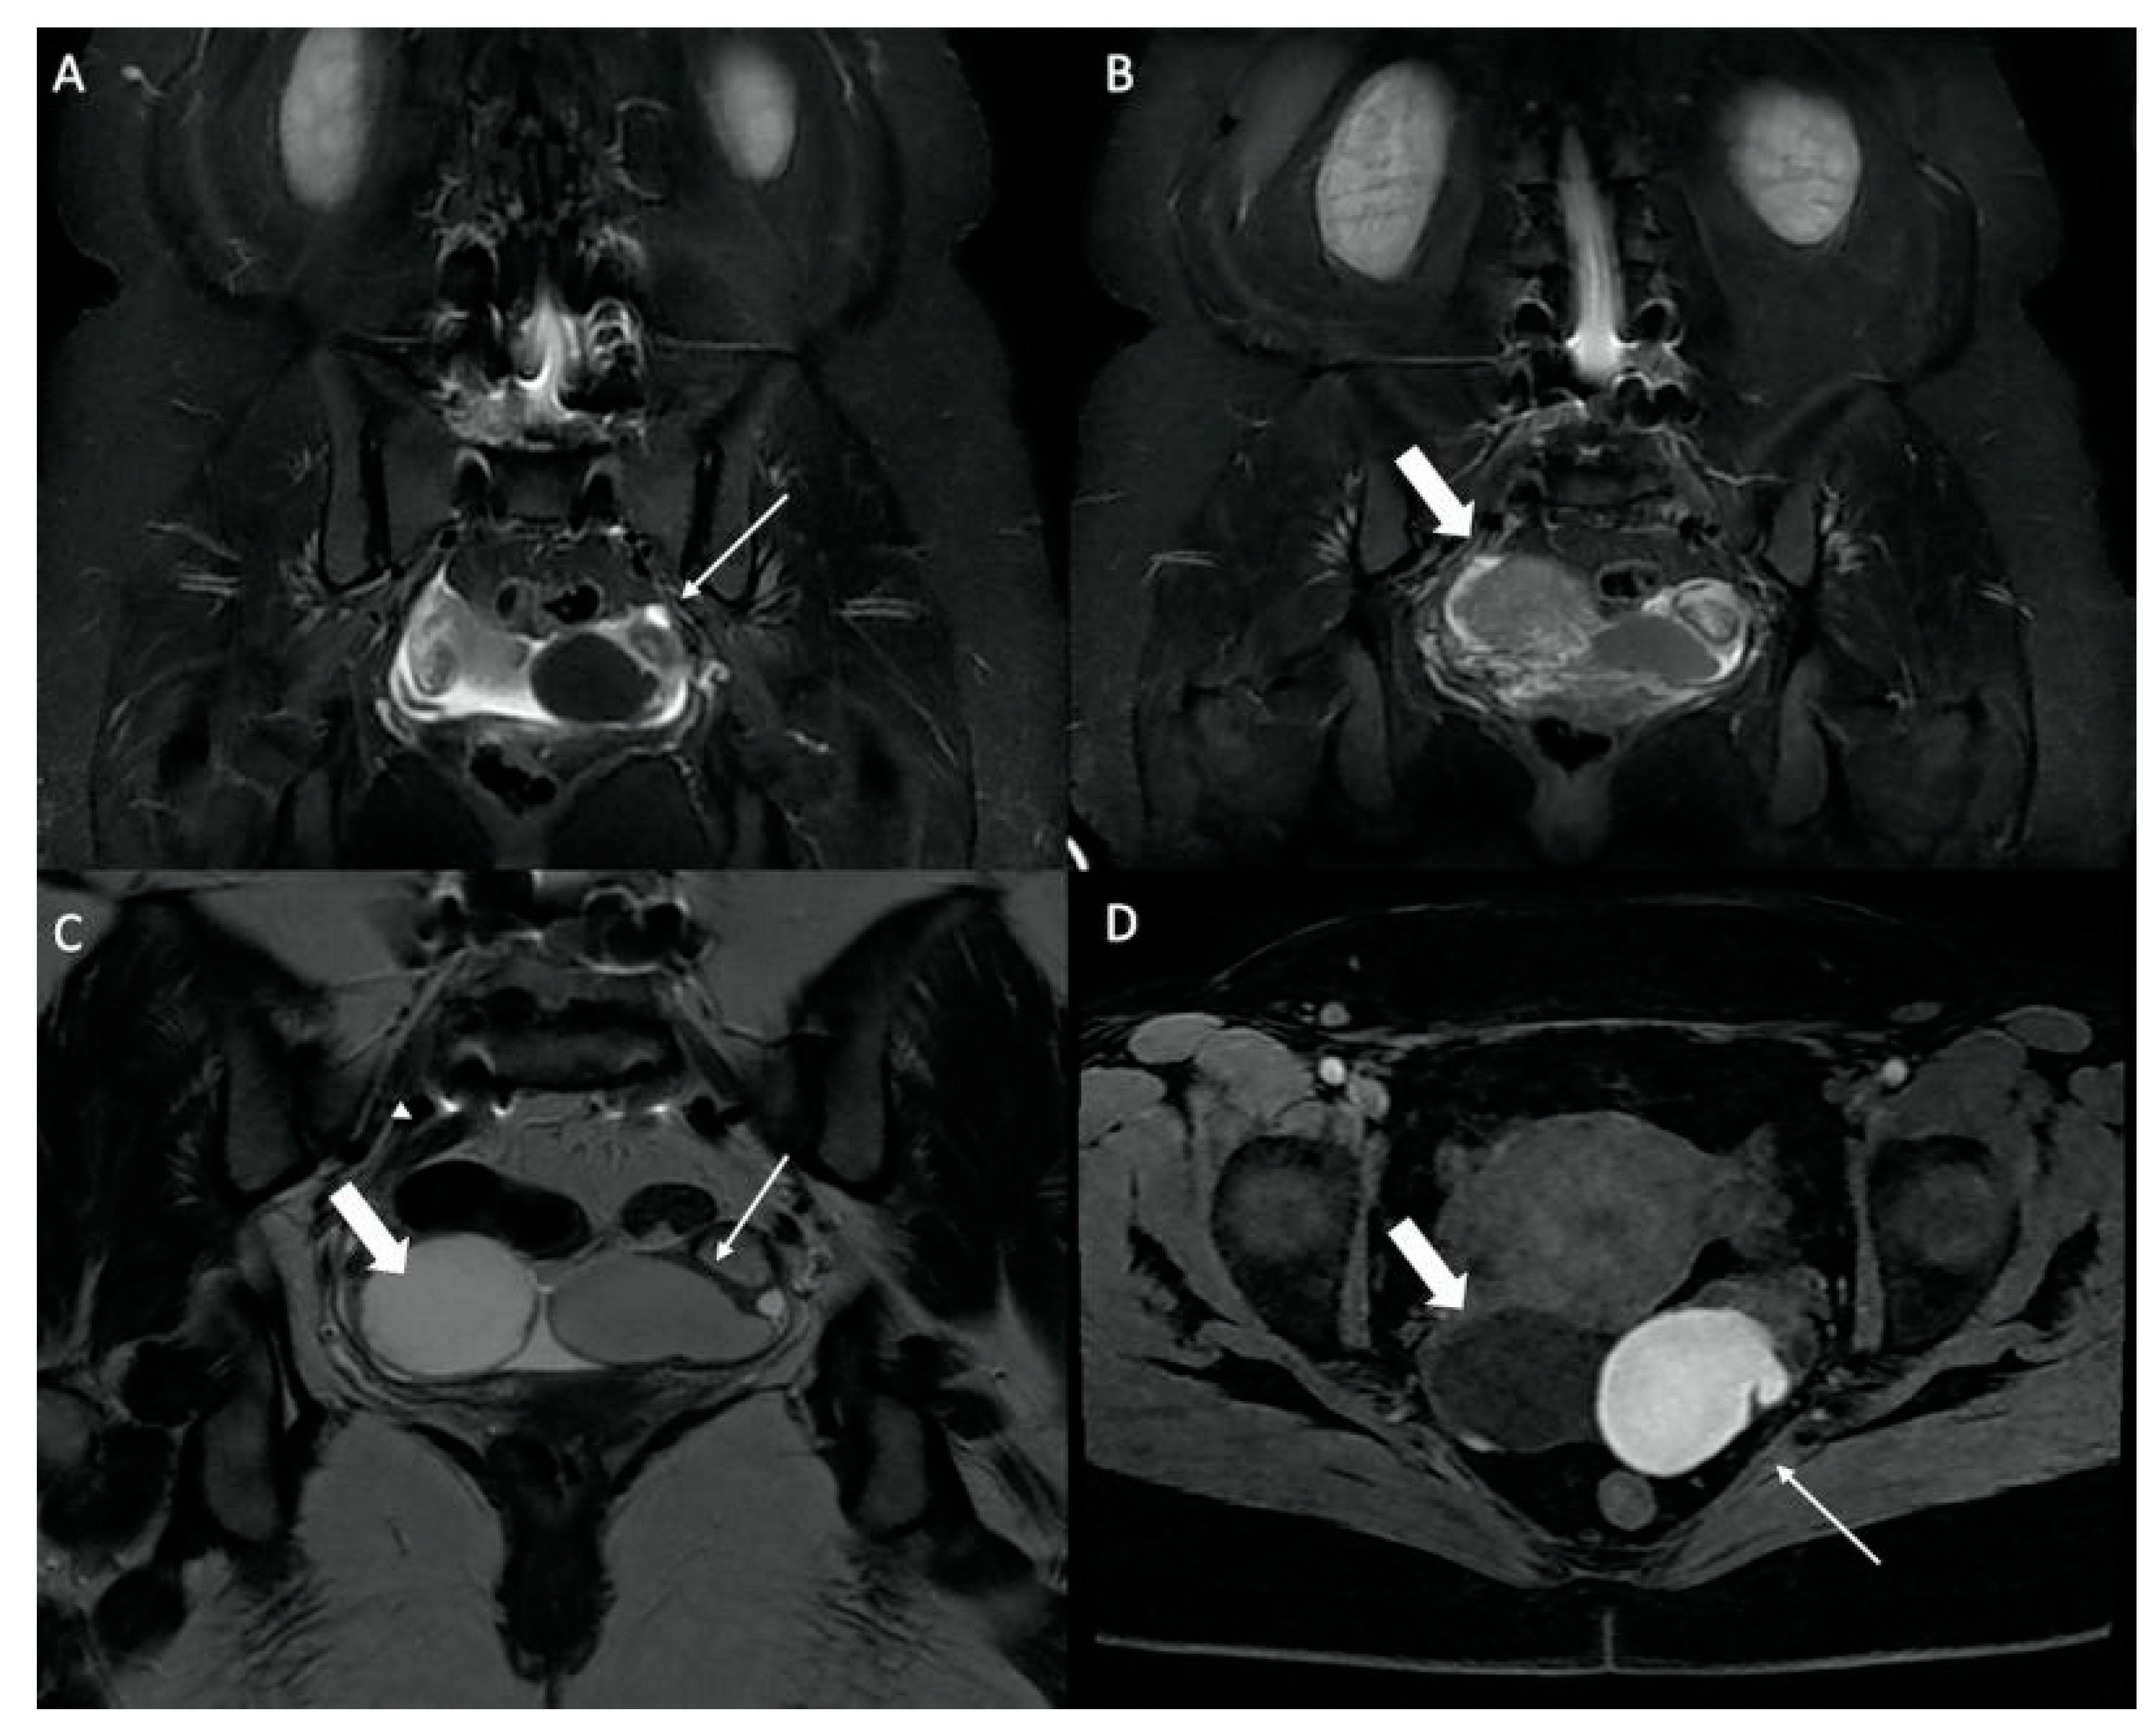

| Hip Joint | Congestive hip osteoarthritis | 17 |

| Stress femoral fracture | 4 | |

| Avascular femoral osteonecrosis | 1 | |

| Extensive acetabular edema | 1 | |

| Gluteal Muscles | Gluteal tendinobursitis | 21 |

| Sacroiliac Joint | Congestive degenerative arthropathy | 10 |

| Inflammatory sacroiliitis | 4 | |

| Sacral fracture | 1 | |

| Pubis | Septic arthritis of the pubis | 1 |

| Femur | Periprosthetic loosening fracture (total hip replacement) | 1 |

| Greater trochanter fracture | 1 | |

| Mixed Musculoskeletal Causes | Inflammatory sacroiliitis and gluteal tendinobursitis | 1 |

| Degenerative congestive sacroiliac arthropathy and gluteal tendinobursitis | 1 | |

| Others | Endometrioma with posterior deep pelvic endometriosis | 1 |

| Ischio-femoral impingement | 1 | |

| Retroperitoneal mass syndrome with urinary obstruction | 1 |